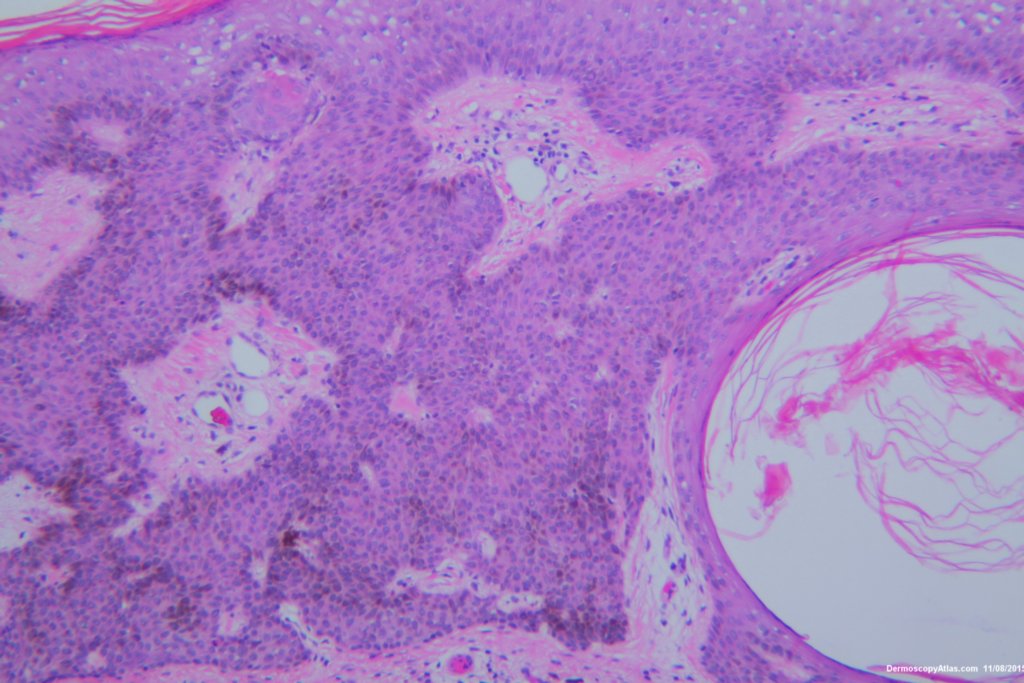

Diagnosis: Seborrhoeic keratosis irritated

This lesion looked darker than the many other seborrhoeic keratoses on this elderly man's back. It was thought there might be a lentiginous proliferation of atypical melanocytes in the lesion . Also the multiple colours and the white lines were unusual for a seborrhoeic keratosis. However pathology of a large shave biopsy excision showed only a pigmented thick seborrhoeic keratosis with increased pigment in normal basal keratinocytes. The blue colour was because of the depth of the lesion ie thick. No idea why the white lines!